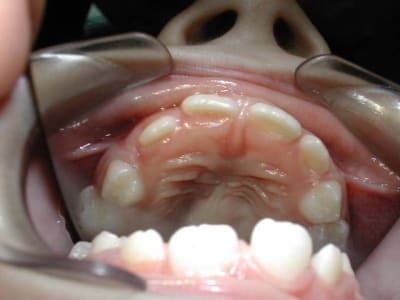

J'ai une petite patiente de 8 ans qui a 54 et 64 à l'état de racines car apparemment elles n'avaient été reconstituées qu'au cavit dans un autre cabinet au lieu de coiffes. Résultat:je vais devoir extraire et faire des mainteneurs d'espaces. Question: est-il mieux de faire 2 mainteneurs unilatéraux ou un seul bilatéral? J'ai déjà entendu des dentistes qui plutot que de mettre un mainteneur d'espace préféraient laisser la dent telle quelle malgré un délabrement très important pour maintenir l'espace, ce qui est manifestement le cas de ma patiente. C'est vrai qu'il y a très peu de cabinets où ils font des endo sur dents temporaires!

En cas d'éxtraction de 54/64, je ferais Bagues sur 6 + arc lingual. Mais on peut aussi faire deux mainteneurs d'éspace, dans certains cas.

Pour 54/64, je ferais 2 mainteneurs d'épace.

2 unilatéraux, pour ne pas gêner la croissance frontale naturelle des mx. Qd à la distance M-D, elle est svt compensée par la création naturelle de diastèmes entre les dents lactéales qui survivent sur l'arcade.